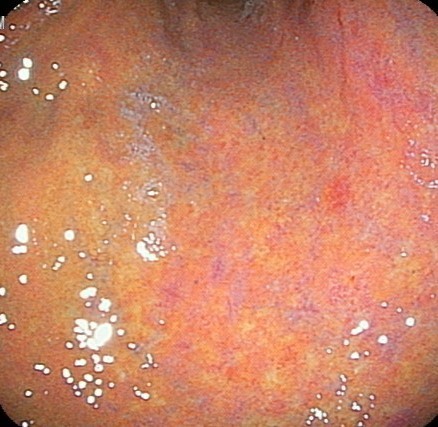

最新レーザー内視鏡による粘膜観察

ピロリ感染による胃炎後は凹凸も多く

胃がんが隠れやすい粘膜となります。

そのため正確な内視鏡観察が必要です。

レーザー内視鏡による早期胃癌の診断

非常にわかりにくい

胃癌の形態を示しています

除菌後胃がんは凹凸のある粘膜の中で発見しにくいため、内視鏡を専門に行っている施設で内視鏡検査を受けることが勧められます。また最新の内視鏡技術として胃炎をより強調し、その中に胃がんを目立たせて色の違いとして浮かび上がるように発見しやすくするレーザー内視鏡による最新技術があります。このシステムにより胃炎で荒れた胃の粘膜の中から、早期胃がんを発見することが可能となってきています。

当院でも積極的にこの内視鏡システムを導入しています。レーザー内視鏡の導入で、従来暗くなりがちだった細経内視鏡でもしっかり胃内の観察ができます。早期胃癌を発見することもしばしばあります。